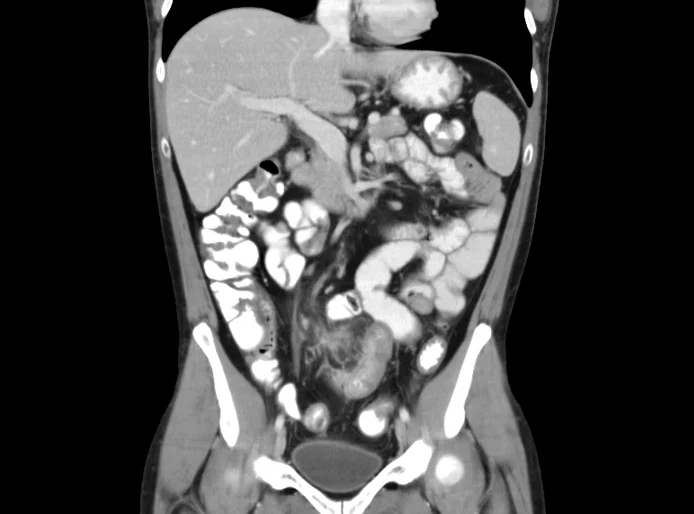

Abdominal imaging – workstation-based – case-based review of bowel obstruction

Coordinators

Dr Anuradha Chandramohan